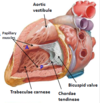

The right ventricle is covered by a number of irregular bridges (trabeculae carneae)

- The right ventricle contains three papillary muscles, which project into the chamber via their heart tendons (chordae tendineae)

- They attach to the edges of the tricuspid valve leaflets & contract to prevent the back-flow of blood